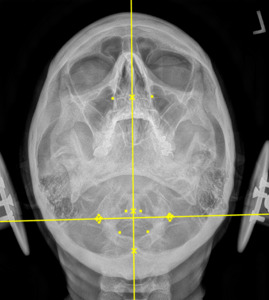

Plain film radiography of the cervical spine showed a grade 1 spondylolisthesis of C4 (Figure 3), mild disc and facet degeneration of C5 (Figure 3), a motion fixation of the C4-C5 vertebrae unit in forward flexion (Figure 4), a retrolisthesis of C3 on extension (Figure 5), and a structural malposition of the craniocervical junction as per Orthospinology measurements. (Figures 6 and 7). Though these are static films and active motion cannot be observed in real-time, motion restriction of the C4-C5 vertebrae unit from neutral to forward flexion position was determined by a lack of spinous separation, a lack of intervertebral foramen expansion, and an absent intersegmental kyphosis of George’s Line.

During the initial examination, the chiropractor evaluates the patient’s postural findings, including standing head tilt, head rotation, shoulder height comparison, hip height comparison, lower neck deviation, and supine leg-length inequality. The chiropractor will then take 3 radiographic images of the CCJ minimum to view the alignment in a projected 3-dimension. These images are the cervical neutral lateral (sagittal plane), the nasium (frontal plane), and the vertex (transverse plane). A series of measurements are graphed on the radiographs to assess for alignment. Then, the Orthospinology upper cervical procedure provides a calculation and vectored angle based on these measurements to reduce the misalignment. The chiropractor will use this angle to administer the adjustment to the CCJ. Immediately after the adjustment, the chiropractor evaluates the postural findings for correction. If it has improved, the chiropractor repeats the nasium and vertex views to observe for structural correction. If the postural findings do not improve, the chiropractor may administer a subsequent adjustment before the post-imaging is taken.12